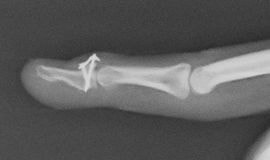

槌指とは木槌(マレット)のように変形した指を指す言葉であり、これには、末節骨の伸筋腱が付着する部位の裂離骨折によっておこるものと、伸筋腱の終止腱の断裂によっておこるものが含まれます。

いずれの場合も、症状はDIP関節の自動伸展障害ですが、放置するとスワンネック変形(白鳥の首様の変形)を生じます。さらに、骨折の場合には早期にDIP関節の変形性関節症を生じる原因となることがあります。

陳旧例で骨の変形癒合がある場合には、骨切術により変形の矯正が可能です。腱断裂の陳旧例では、手術による腱の縫縮あるいは腱移行術によって変形の矯正が図られます。

末節骨変形治癒骨折の骨切術(左:術前・右:術後)